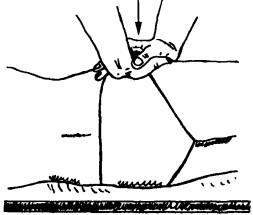

Ábra. 138. kismedencei eltolódás

csavart medence mechanizmus Cramer aszimmetrikus nutáció és forgása a keresztcsont tekintetében mind a kismedencei csontok (ábra. 140). Azon az oldalon, elmozdulás keresztcsont ponyvák előre és lefelé (ventrokaudalno), és másrészt a rendre tolódott felfelé és hátra (dorsokranialno). Azon az oldalon, a dőlés a keresztcsont olyan irányban ventrokaudalnom medence forog kifelé hosszanti tengelye körül a szemközti oldalon ez körül forgatjuk az elülső tengely áthalad a csípőizületi vápa. Ugyanakkor a medence, mintha rastopyrivat, symphysis történik relatív hígítása a szeméremcsont, hogy az aszimmetria a helyüket. Általában úgy tűnik, hogy egy csípő forgatva egymáshoz képest körül az első oldalsó gerinc. Külső forgása a medence az alsó fekvő felső hátsó csípő a legtöbb esetben okoz megfelelő elfordulását a külső lábak. Klinikai tünetek csavart kismedence következő: posterior csípőnyerget és egy hátsó éle a csípő gerincén alatt található az egyik oldalon, és az elülső AWN - az alábbiakban a szemközti oldalon. És csípőtaréj oldalon lehet ugyanazon a szinten. Lehet változatok, ahol akár elöl vagy hátul a gerinc marad szimmetrikus. Ezért a legfontosabb dolog - a hely meg nem felelés az első és hátsó tüskék és a csípőlapátból. Amikor egy csavart medence nem a blokkoló és visszaélés az ő helyzetét.